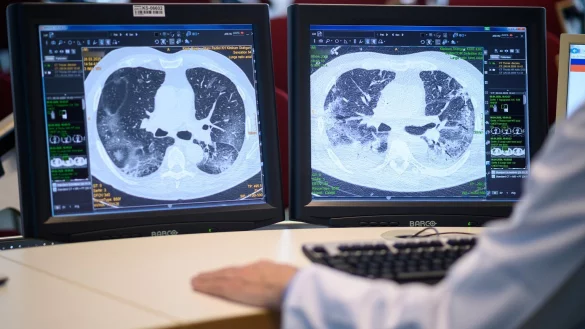

Ist die Lungenfunktion von Covid-19-Patienten so stark eingeschränkt, dass eine solche Versorgung mit Sauerstoff bei zunehmender Atemnot nicht mehr ausreicht, werden sie auf die Intensivstation verlegt und bekommen in ein künstliches Koma versetzt eine Beatmung über einen Schlauch in der Luftröhre. Eine solche Intubation birgt Risiken.

So ist das Aufheben der Beatmung ein schwieriger Prozess - je länger sie dauerte, desto stärker sind neben anderen auch die zum Atmen benötigten Muskeln abgebaut. Gerade bei Älteren ist es schwierig, sie wieder bis zum Zustand zuvor aufzubauen. Auch reagiert die Lunge empfindlich auf Überdruck und auch auf den Sauerstoff, der der Beatmungsluft zugesetzt wird. Lungengewebe kann irreparabel geschädigt werden. Auch in anderen Organen kann eine künstliche Beatmung zu Schäden führen.

Über Langzeitfolgen etwa solcher Lungenentzündungen lassen sich Experten zufolge noch keine gesicherten Aussagen machen. Bei heftigeren Verläufen, etwa mit schwerem Lungenversagen und langer Beatmungsdauer, seien durchaus Restsymptome wie ein vermindertes Lungenvolumen zu erwarten, sagt der Mediziner Sven Gläser vom Vivantes-Klinikum Neukölln.